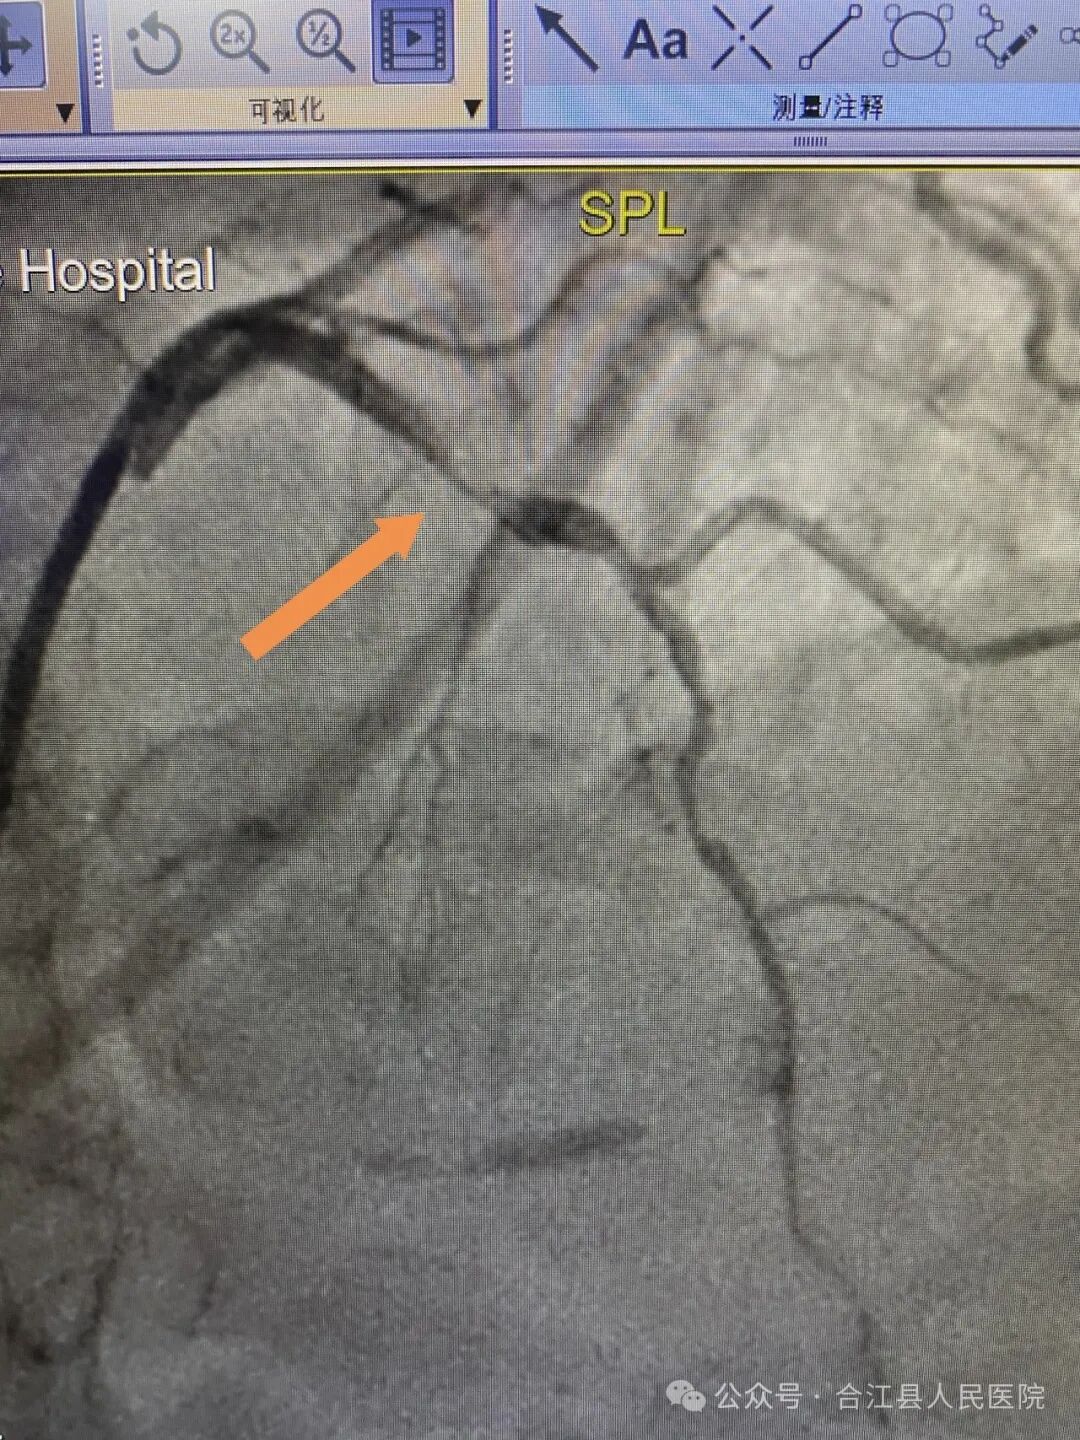

胸痛中心医疗总监、副主任医师张永强火速赶到介入手术室,对老人进行了问询和查体,与家属沟通后决定行急诊冠脉造影,造影结果显示:LAD近段严重狭窄95%。随后,再次取得患者家属同意后,经验丰富的张永强对其成功实施了急诊冠脉支架植入